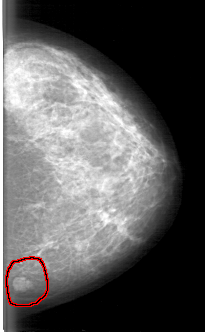

D_4082_1.RIGHT_MLO

FILE: D_4082_1.LEFT_MLO.OVERLAY

TOTAL_ABNORMALITIES 1

ABNORMALITY 1

LESION_TYPE MASS SHAPE LOBULATED MARGINS MICROLOBULATED

ASSESSMENT 3

SUBTLETY 5

PATHOLOGY BENIGN

TOTAL_OUTLINES 1

BOUNDARY

LEFT_MLO LINES 5326 PIXELS_PER_LINE 3421 BITS_PER_PIXEL 12 RESOLUTION 43.5 OVERLAY